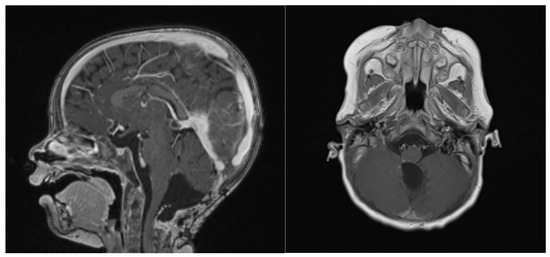

The second-look surgery was uneventful. The child weighed 9 kg and was 76 cm tall. A millimetric residual tissue was left in place, infiltrating the floor of the IVth ventricle at the bulbo-pontine junction on the right. Blood loss was estimated to be around 50 mL, whilst the patient was transfused with 2 RBC and of 1 PLT concentrate. A new postoperative MRI confirmed a millimetric enhancement at the right bulbo-pontine junction (Figure 6).

Figure 6.

Second surgery: postoperative Gadolinium T1 and substraction sequences showing a GTR without complications.